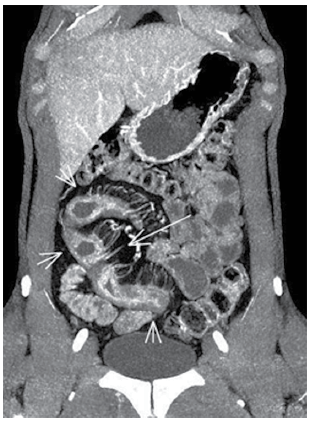

Dor abdominal constante e, às vezes, episódios de diarreia. Nesse caso, considerando-se a imagem a seguir, o diagnóstico mais provável é:

Provas